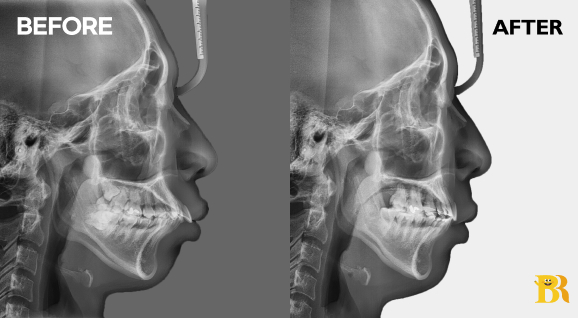

[상악 전치부가 앞쪽으로 크게 뻗은 케이스] 입술이 도드라져 보여서 발치교정으로 앞니의 각도를 감소시켜 주었습니다